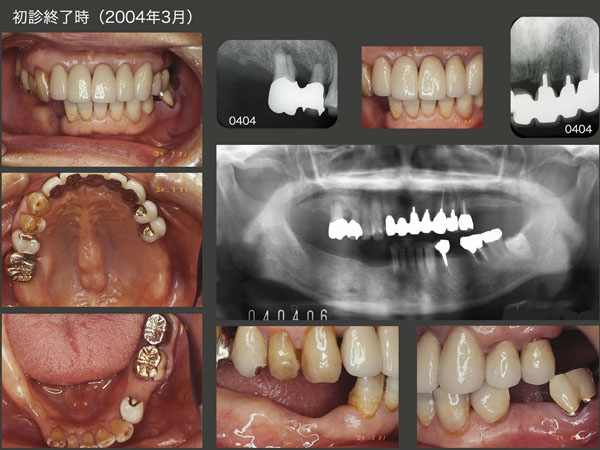

まず,人工歯を旧義歯に付与することで,上顎前歯の審美回復を図った.つぎに,右上6を近心に移動した.移動にかかった期間は約1ヵ月と早いが,その位支持歯槽骨がない状態であった.さらに,左上1,2および4の歯冠長を延長し,歯肉縁上歯質の確保を行った.2003年5月,基礎治療が終了し,ここから最終補綴装置の製作にとりかかった.

初診終了後約7年間は特に問題なく経過した.しかし,2011年2月に,まず左下4のメタルボンド冠の陶材が少し破損した.しかし,特に支障がないのでこのまま経過をみることにした.右下は犬歯以降が失われているため,どうしても咬合・咀嚼の中心は左側の咬合支持歯にならざるを得ない.したがって,左下4の存在するエリアに常に咬合力が加わるため,トラブルが生じやすい.